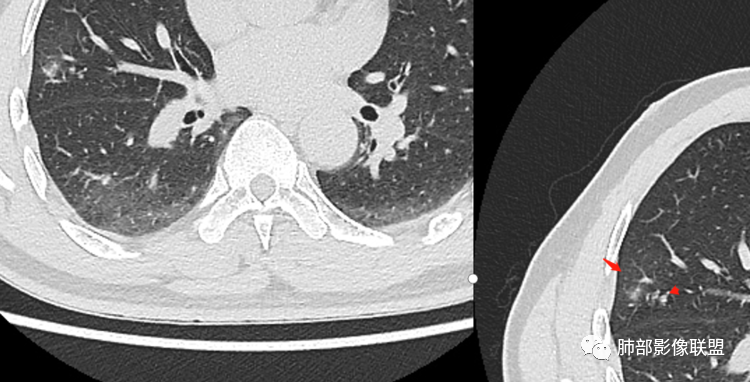

3、卫星灶与“蘑菇兄弟”:诊断隐球菌时,建议找卫星灶,卫星灶可以在遥远的地方。可以是遥远地方的微小结节——“小蘑菇兄弟”。有些远处的卫星灶,通常是不规则饱满实性的,晕征不明显。隐球菌的卫星灶非常“隐”,但发现率高达60%多,诊断价值高。

4、卫星灶距离远的原因:隐球菌卫星灶常很远,推测:一次空气来源隐球菌感染进入双肺多处,部分定居繁殖;距离近的隐球菌“蘑菇兄弟”常常是二次感染。

5、周围毛刺纤维、边缘形态等:坏死包裹会使得结节变圆;结节多缺乏明显的分叶征,缺乏局部突出生长能力;如果出现分叶,是由多处肉芽肿中心形成。没有坏死的局限化,结节只是凑合在一起,常呈方形征;毛刺进入晕区(概念源自南边老师),毛刺较短、较软;周围的晕吸收后,会留下不规则边,外面常残留丝状条索;收缩力较弱,临近胸膜对胸膜牵拉不明显。

6、隐球菌的毛刺消失于晕区的解释:隐球菌结节周围有间质淋巴细胞增多,肉芽肿性炎延伸,以及纤维组织增生,形态并不规则,不是因为收缩力。